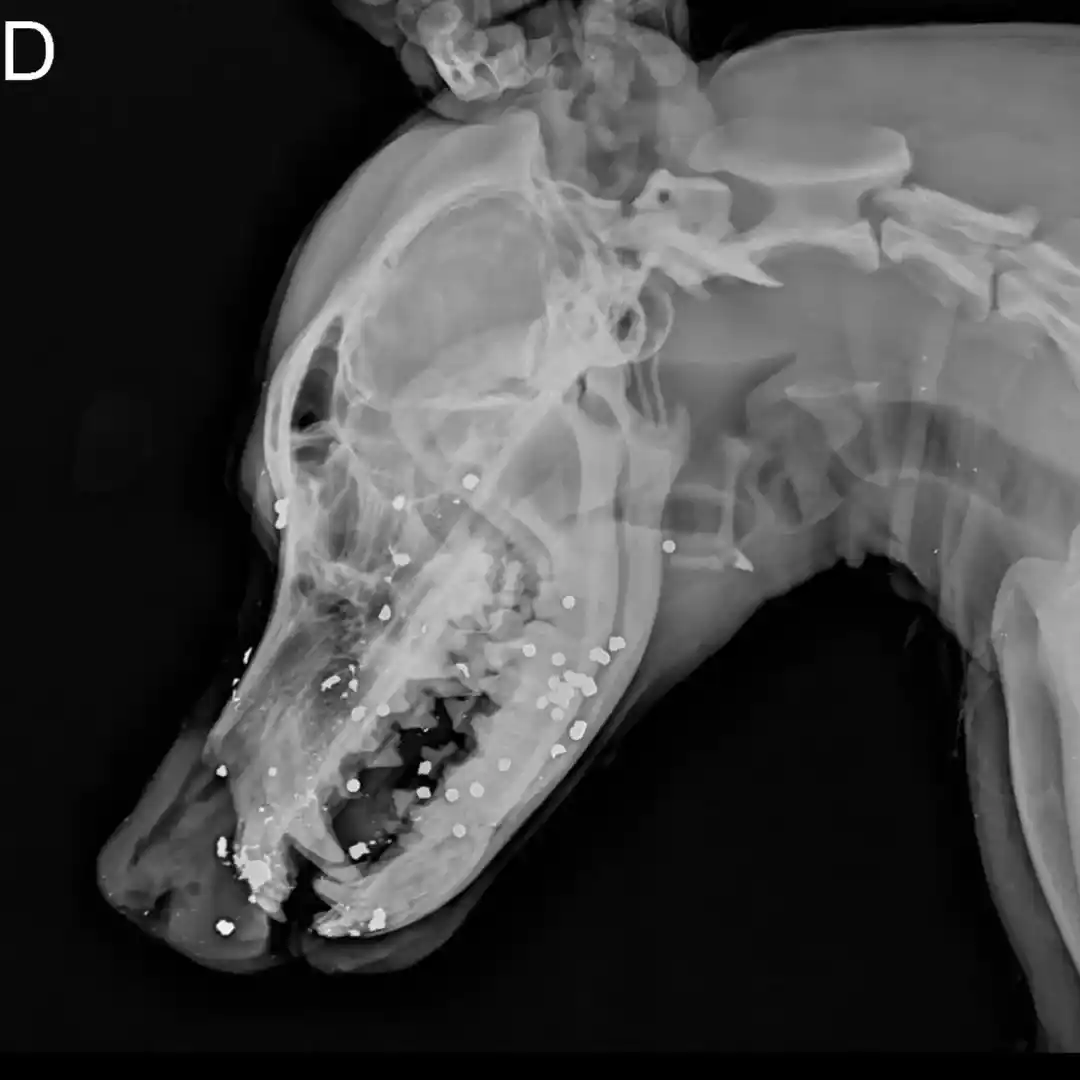

"Las placas hablan por sí solas", expresaron desde Mascotandil. Los estudios muestran que el animal recibió un disparo con una escopeta y tiene los perdigones dispersos por toda la cara. Los profesionales indicaron que fue muy difícil frenar la hemorragia.